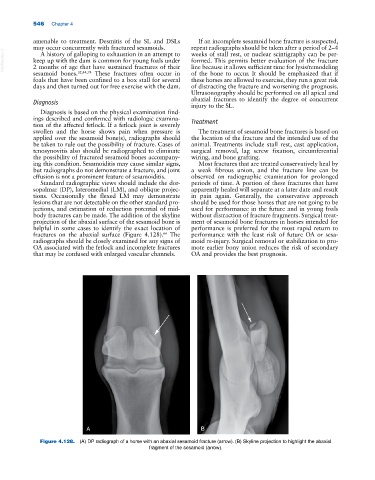

Standard radiographic views should include the dor- periods of time. A portion of these fractures that have

sopalmar (DP), lateromedial (LM), and oblique projec- apparently healed will separate at a later date and result

tions. Occasionally the flexed LM may demonstrate in pain again. Generally, the conservative approach

lesions that are not detectable on the other standard pro- should be used for those horses that are not going to be

jections, and estimation of reduction potential of mid- used for performance in the future and in young foals

body fractures can be made. The addition of the skyline without distraction of fracture fragments. Surgical treat-

projection of the abaxial surface of the sesamoid bone is ment of sesamoid bone fractures in horses intended for

helpful in some cases to identify the exact location of performance is preferred for the most rapid return to

fractures on the abaxial surface (Figure 4.128). The performance with the least risk of future OA or sesa-

Figure 4.128. (A) DP radiograph of a horse with an abaxial sesamoid fracture (arrow). (B) Skyline projection to highlight the abaxial

fragment of the sesamoid (arrow).